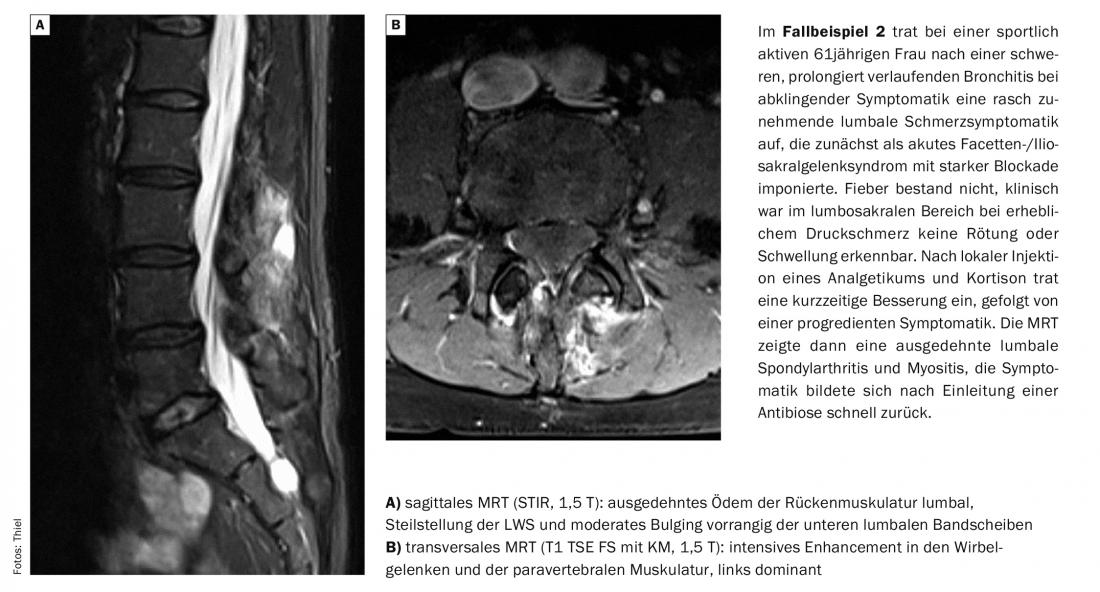

Le miopatie infiammatorie sono sempre più osservate come complicazione dell’infezione da HIV, fino al 72% dei casi [2]. Dal punto di vista dell’immagine, la miosite ascessuale può essere difficile da distinguere dal miosarcoma con necrosi tumorale [3].

La miosite focale si differenzia per il modello di coinvolgimento (singolo muscolo o compartimento muscolare interessato) e mostra un chiaro aumento del contrasto senza ascesso o necrosi del tessuto. Sono colpiti soprattutto i singoli muscoli della parte inferiore della gamba. Le calcificazioni sono comuni nella miosite parassitaria e le intense reazioni di contrasto accompagnate da necrosi tissutale e ascessi sono quasi regolari nella miosite indotta da agenti patogeni. Le reazioni del tessuto edematoso richiedono l’uso di sequenze a soppressione di grasso per una rilevazione affidabile [9]. Tuttavia, l’evidenza di edema non è solo un’espressione di infiammazione, come mostra la Tabella 1 in termini di diagnosi differenziale.